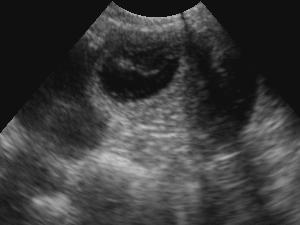

We offer a mobile service of Ultrasound Scanning in the comfort of your own home. Confirming pregnancy in your Bitch from Day 28 from Mating. £40 per scan plus travel expenses if applicable. (free within 10 miles) DEFRA approved. VIS trained and Certified. High Specification Veterinary Equipment

We offer a service where we can come to your own home and Scan your bitch for pregnancy. We can confirm if your bitch is in pup and can give a rough estimate on how many pups can be seen. However, we cannot be held responsible for the accurate number of pups as bitches can reabsorb pups as well as pups can be hidden.